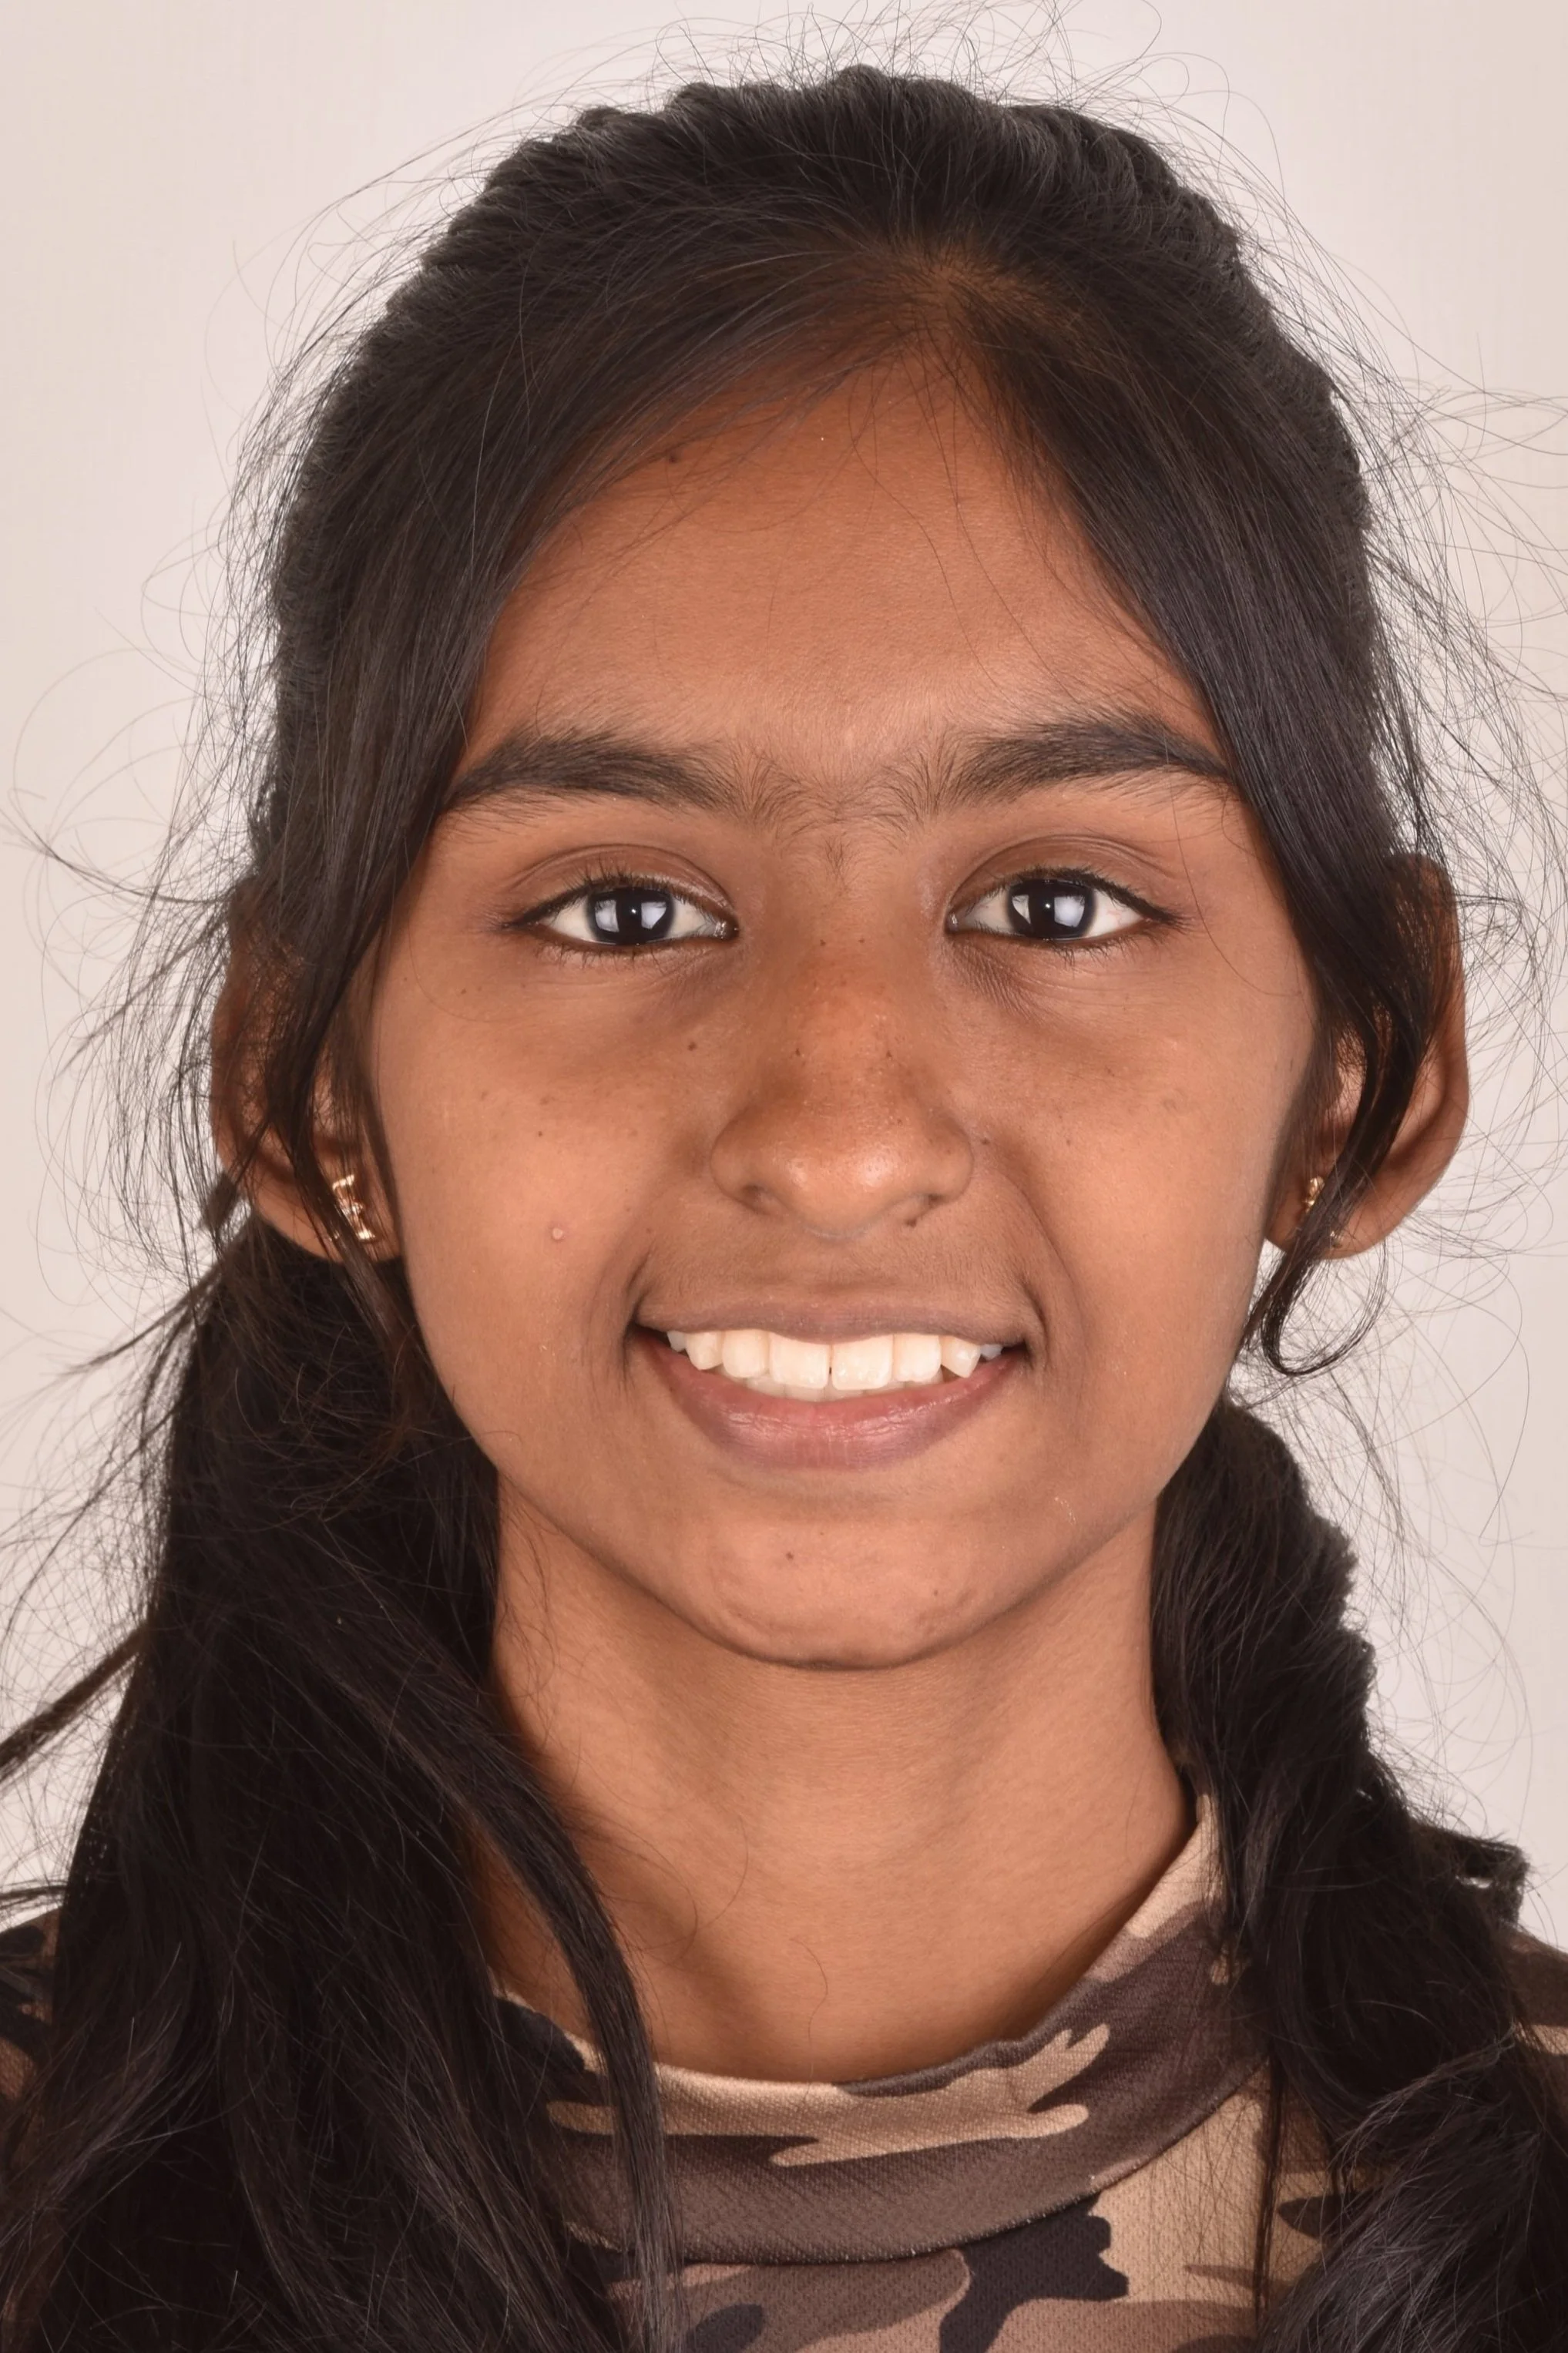

smile makeover

Smile Journey!

May be it is too simple to treat but the way this smile makeover made a difference in her life is immense! thats how wonderful smile curves are created!